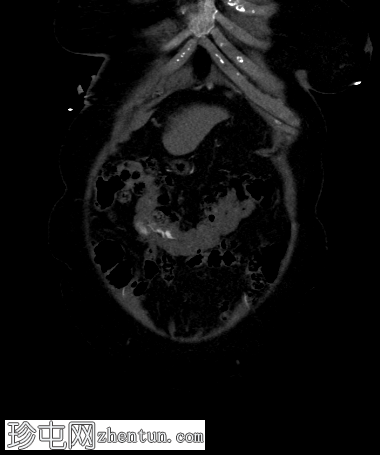

冠状位增强扫描

动脉期

弥漫性结肠憩室病,无憩室炎证据。

横结肠中段可见一憩室,动脉期开始出现异常造影剂外渗,门静脉期增多,憩室腔内亦可见造影剂外渗,提示憩室出血伴活动性动脉出血。

患者既往有结肠憩室炎病史,此次因新鲜下消化道出血就诊。行CT血管造影以确定出血部位和出血来源。出血始于乙状结肠憩室,腔内渗出的造影剂与乙状结肠腔内的造影剂相连。随着造影剂显影的进行,憩室逐渐被完全充盈,乙状结肠腔内渗出的造影剂增多,符合活动性动脉出血的表现。

服用抗凝剂、非甾体抗炎药以及患有弥漫性结肠憩室病的年长患者发生结肠憩室出血的风险较高。无需特殊准备即可立即进行多期增强CT扫描,其在检测和定位消化道出血源方面具有很高的特异性,因此有助于对这些患者进行分诊,并改善治疗性结肠镜检查的疗效。